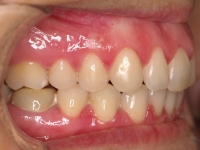

Premolar mandibular incluido + fenestración

45 incluido